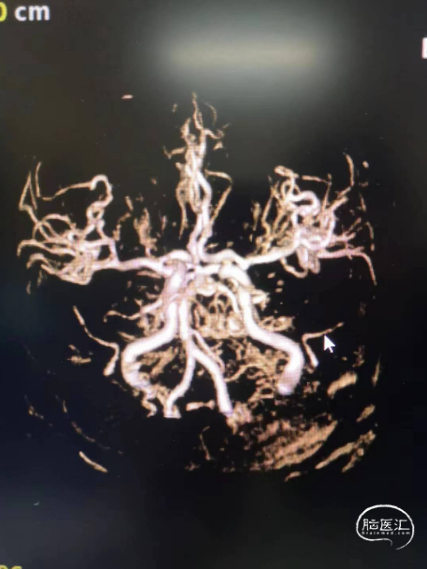

符合脑内多发缺血变性灶、梗死灶(左侧大脑半球大面积急性梗死)、软化灶T2-FLAIR/DWI表现;

符合颅脑动脉硬化并多发狭窄MRA表现,左侧颈内动脉颅内段、大脑中动脉及分支未见显示,考虑闭塞或重度狭窄,建议CTA进一步检查。

造影显示左侧的颈内动脉末端闭塞,中间导管造影显示大脑前和大脑中动脉显影,明确颈内末端闭塞。